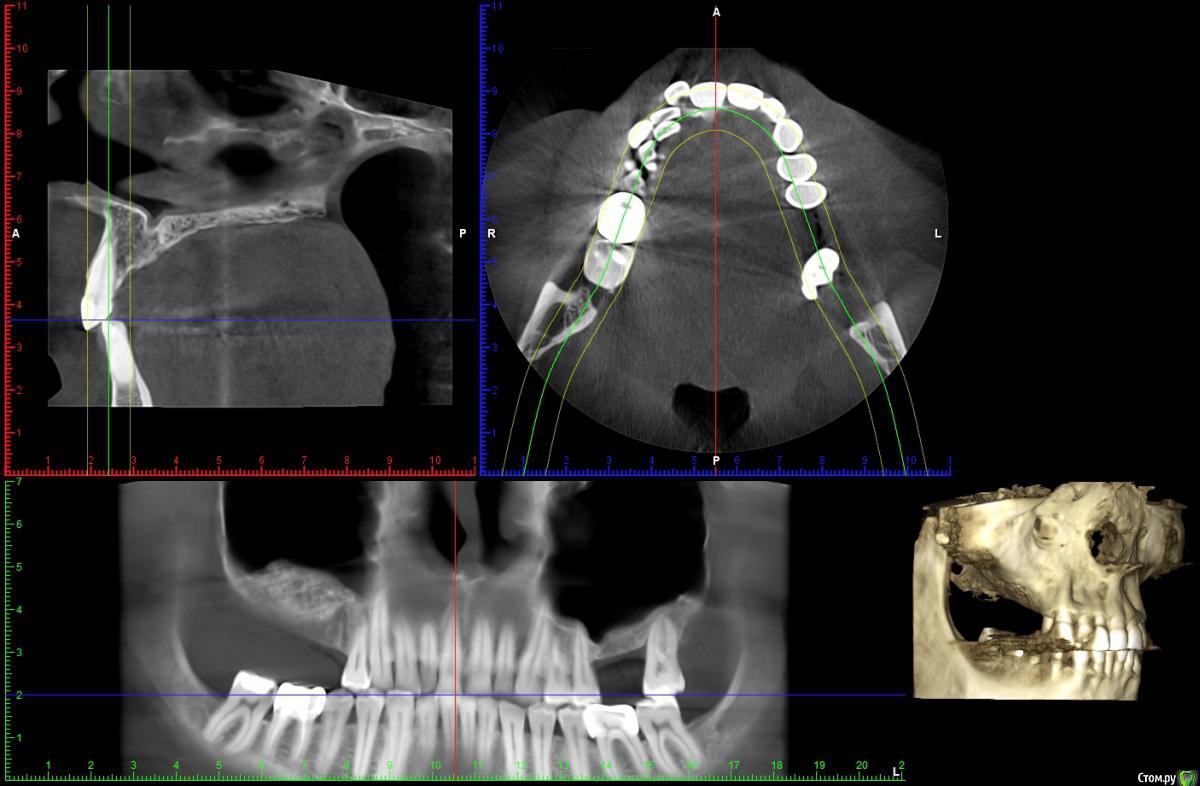

Reyb Опубликовано 14 марта, 2018 Поделиться Опубликовано 14 марта, 2018 Здравствуйте уважаемые доктора.У меня такая проблема,в декабре 2016 года мне делали открытый синус лифтинг справа.Через день-два после операции у меня начались боли,что я воспринял как норму.Дней через 9 врач снял швы,осмотрел и сказал,что всё в норме и боли должны скоро пройти.Через месяц,когда стало можно сморкаться,сразу заметил что справа высмаркивается слизь с кровью,да и к тому же боль не проходила.Пошёл к своему врачу.Он осмотрел и сказал,что всё в приделах нормы (по панорамному снимку).Спустя 1,5 месяца,при сморкании стал замечать ещё и гной с кровью.Спустя ещё где-то 2-3 недели периодически стало закладывать нос.Когда подошло время ставить импланты врач посмотрев КТ сказал,что нельзя,так-как гайморит справа и направил к лору.Пролечившись у лора,стал сомневаться в продолжении имплантации.Спустя 15 месяцев ноющая боль на стороне операции осталась и при сморкании иногда что-нибудь да вылетит из правой ноздри (сгустки крови или почти сухая корка в слизи).На сегодняшний день как и с первых дней после синус лифтинга самочувствие как-будто приболел,писк в ушах(появлялся всегда когда чем-нибудь болею).На КТ просматривается неоднородность и затемнения в материале.Что это,отторжение,инфицирование или норма?К своему стоматологу претензий не имею так-как сделано было на мой взгляд на высоком уровне.Что посоветуете делать в моём случае? КЛКТ от 1.03.2018г.http://my-files.ru/qki4xs Ссылка на комментарий

wladdX Опубликовано 15 марта, 2018 Поделиться Опубликовано 15 марта, 2018 Несколько скринов Ссылка на комментарий

Irouil Опубликовано 15 марта, 2018 Поделиться Опубликовано 15 марта, 2018 Когда КТ делали? У Вас открыт нижний носовой ход в пазуху, уже это одно может вызывать выделения из ноздри, на которые Вы жалуетесь. Да и болевые ощущения, в принципе. Кажется графт не звонил, слизистая спокойная вокруг него, но может быть и не пророс новой костью. Надо готовиться под имплантацию, я считаю, если при сверлении обнаруживается несостоятельность графта - удаление его из пазухи и реоперация через месяц Ссылка на комментарий

Reyb Опубликовано 15 марта, 2018 Автор Поделиться Опубликовано 15 марта, 2018 Когда КТ делали? У Вас открыт нижний носовой ход в пазуху, уже это одно может вызывать выделения из ноздри, на которые Вы жалуетесь. Да и болевые ощущения, в принципе. Кажется графт не звонил, слизистая спокойная вокруг него, но может быть и не пророс новой костью. Надо готовиться под имплантацию, я считаю, если при сверлении обнаруживается несостоятельность графта - удаление его из пазухи и реоперация через месяц Когда КТ делали? У Вас открыт нижний носовой ход в пазуху, уже это одно может вызывать выделения из ноздри, на которые Вы жалуетесь. Да и болевые ощущения, в принципе. Кажется графт не звонил, слизистая спокойная вокруг него, но может быть и не пророс новой костью. Надо готовиться под имплантацию, я считаю, если при сверлении обнаруживается несостоятельность графта - удаление его из пазухи и реоперация через месяцКТ делал 1 марта 2018г. До синуслифтинга выделений не было.Такого чтоб самопроизвольно из носа текло,нет.Только при сморкании бывает,что вылетит не большой сгусток крови. Ссылка на комментарий